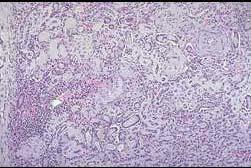

该肾病理图片你考虑哪种情况可能 ( )A.终末肾B.急性肾小管坏死C.新月体性肾炎D.毛细血管内增生性肾小球肾炎E.局灶性节段性硬化

选项 A.终末肾 B.急性肾小管坏死 C.新月体性肾炎 D.毛细血管内增生性肾小球肾炎 E.局灶性节段性硬化

答案 A